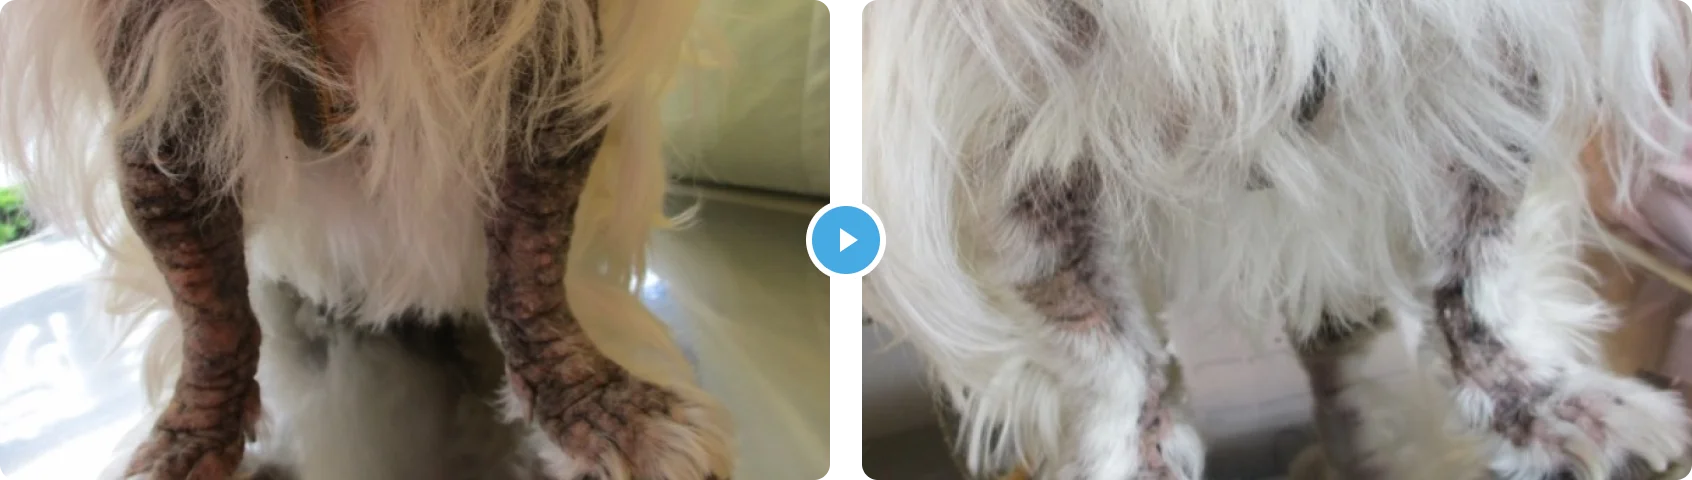

しょくもつアレルギー+アトピーせいひふえん+しろうしょう 食物アレルギー+アトピー性皮膚炎+脂漏症

- 症状の説明

- 治療の内容

老齢期に入り内服薬の副作用も懸念されており、また今まで効果があまりみられなかったので、他の方法での治療をご希望でした。

治療には数カ月かかりましたが、徐々に掻痒は軽減し、皮膚の状態も改善され発毛がみられました。

その後は通院間隔をあけて維持しています。アトピー性皮膚炎や脂漏症は完治せず、歳を追うごとに悪化する傾向があります。また、思ったような効果がでず、治療が長期にわたるため、犬達にも飼い主様にも負担がかかる疾患です。治療は薬浴や内服だけではなく、外用療法も取り入れることで良好にコントロールができる場合があります。